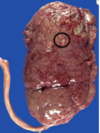

Yellow - white cortical abscesses Surrounding hyperaemia Acute pyelonephritis

75

Acute pyelonephritis Neutrophils seen in renal tubules and interstitium Glomerular involvement suggests severe disease Tubular necrosis leads to scarring